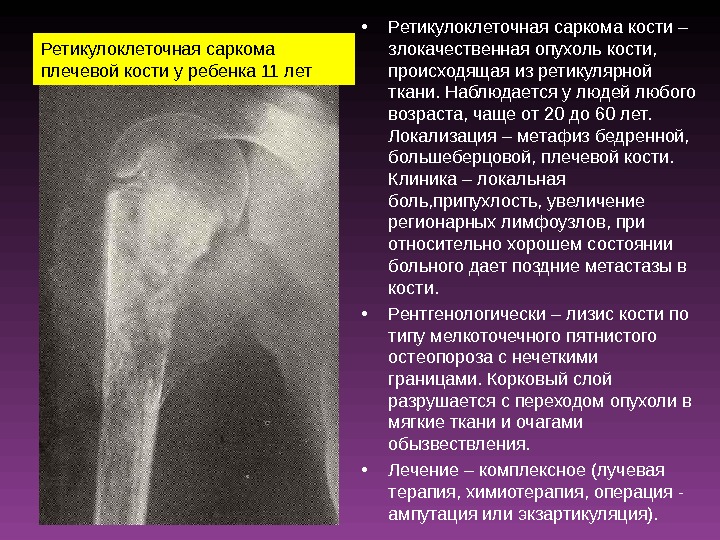

Рентгеновские снимки саркомы плечевого сустава